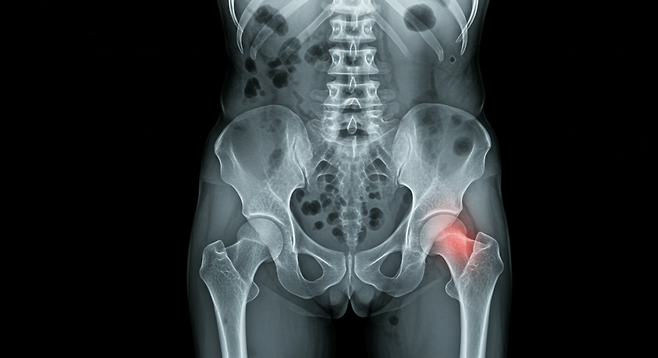

"뼈가 부러질 때까지 몰랐어요." 70대 김모 씨는 넘어지면서 손목이 부러진 후에야 자신이 심각한 골다공증 환자라는 사실을 알게 되었습니다. 평생 우유도 열심히 마시고 칼슘제도 챙겨 먹었는데 왜 이런 일이 생겼을까요? 놀랍게도 그 답은 매일 식탁에 오르는 평범한 반찬들에 숨어있었습니다.

나트륨을 과다 섭취하면 신장에서 나트륨을 배출하려고 합니다. 이 과정에서 칼슘도 함께 소변으로 배출되어 버립니다. 몸속 칼슘이 부족해지면 우리 몸은 뼈에서 칼슘을 빼내어 혈중 칼슘 농도를 유지하려고 합니다. 결국 뼈는 점점 약해지게 되는 것입니다.

특히 한국인의 나트륨 섭취량은 WHO 권장량의 2배가 넘어 더욱 심각한 문제입니다. 매일 먹는 김치 한 접시만으로도 하루 권장량의 상당 부분을 섭취하게 됩니다.